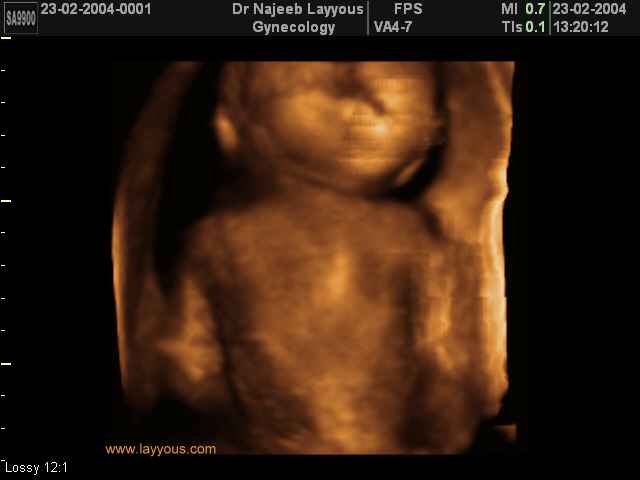

3D Photos échographie des parties du fœtus | Dr N Layyous

3D Photos échographie des parties du fœtus